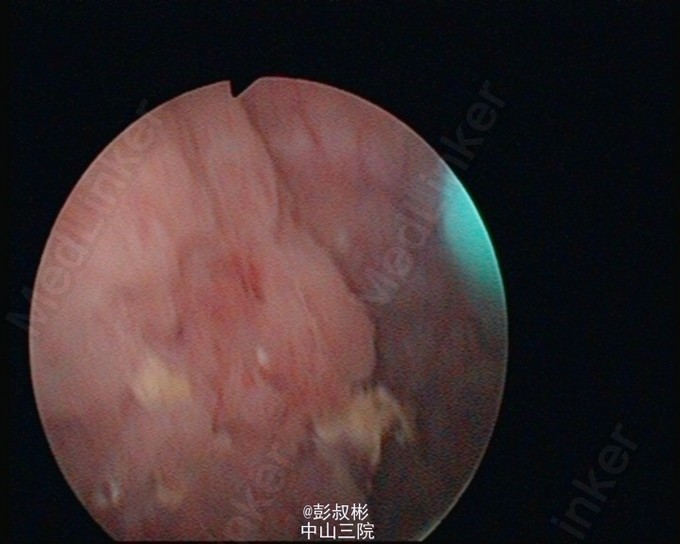

膀胱肿瘤电切实录--看看膀胱癌长这样

主诉 病史

68岁,男性,反复肉眼血尿3个月。盆腔CT:膀胱左前下侧壁约20×21×21 mm肿块,考虑膀胱癌可能性大。术前诊断:膀胱癌。患者合并心肺功能不全,要求保留膀胱。